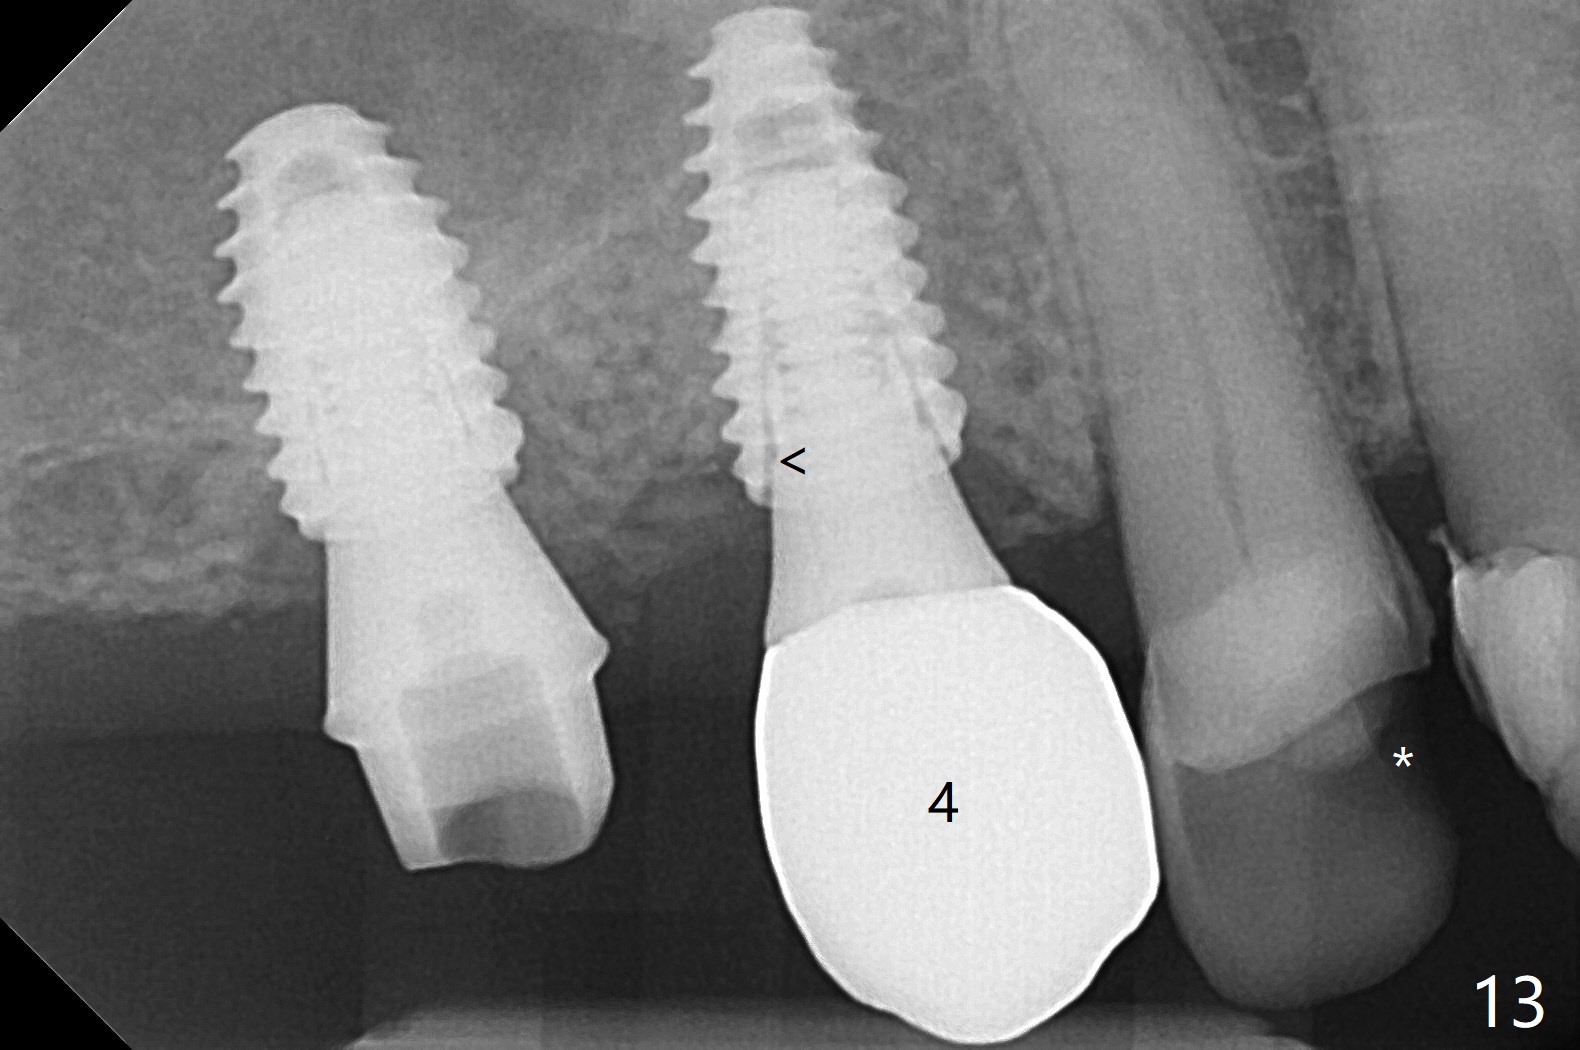

Osteotomy at #3 is performed last (Fig.1,2); as planned, a 4 mm cortical tap is used with guide for sinus lift. Unfortunately the sinus membrane is perforated. Implant placement is aborted. Instead Osteogen plug is inserted into the osteotomy, which is fixed in place by acrylic extending from the provisional at #4. Osteotomy for #3 implant will be attempted with control of the depth in 4 months. The patient has allergy to Amoxicillin (rash). When switching to Clindamycin, she develops diarrhea and loses 10 pounds. There is no abnormality at the site of #3 or 4 nearly 3 months postop (Fig.3). The next surgery will be most likely conducted without antibiotic 4 months postop. Try to draw blood for PRF. Take PA for #12 and 13 for possible impression. Remove the 3 temporary crowns, seat the guide across the arch and use no-stop fixture mounts at #4, and possibly 12 and 13. Follow the original drill sequence (check perforation after each drill, Fig.11) and use DIONavi sinus approach kit. Also load an appropriate stop for the round bur for sinus lift before hand. Mixture allograft with Metronidazole and PRF. In fact everything goes on as smoothly as planned. Osteotomy at #3 is underprep (3.5 mm in diameter drill instead of 4.0). The sinus floor appears to remain to be absent; 3.2 mm round bur is used for lift, alternating with water pumping. Following insertion of 3 pieces of PRF membranes and Vanilla Graft (Fig.4 *), a 4x10 mm dummy implant is placed. After additional bone graft (Fig.5 *), a final 4.5x7.3 mm implant is placed ~10 Ncm. The implant is placed deeper ~ 1 mm, followed by a 5.5x3 mm healing abutment (Fig.6). The implants at #12 and 13 seem to have osteointegrated (Fig.7). Impression is taken for #4, 12 and 13 with limited vertical space (Fig.8,9). An implant at #14 is being considered. There is faint bone graft around the apex of the implant 4 months postop (Fig.10). The implant sustains 25-30 Ncm torque when a 5.2x4(3) mm cemented abutment is placed. A permanent crown is cemented nearly 5 months postop (Fig.11). For the best cosmetic and masticating results, the occlusal surface should have certain degree of morphology, such as the buccal cusps (Fig.12 white curved lines). The abutment at #3 is placed and torqued to 30 Ncm before re-cementation of the repaired crown (increased occlusal surface contact). In fact the abutment at #4 is incompletely seated with a gap (Fig.13 <). The composite at #5 is dislodged while #3 crown is being repaired (*). The abutment at #4 is loose >1 year post cementation. The abutment remains incompletely seated (gap and longer apical space (double arrows)) when the abutment/crown complex rotates lingual mesiobuccal (Fig.14 curved arrow). Further proximal reduction and lingual rotation distobuccal leads to complete seating (Fig.15). It appears that incomplete seating at #13 is associated with hex mismatch (Fig.16, large apical space), which will be fixed next visit. One week later, the crown and abutment of #4 are seated together after crown repair (Fig.17). Since the abutment margin is subgingival, the crown is cemented, removed with abutment for residual cement removal and reseated with the abutment with torque at 30 Ncm. After this, the crown and abutment of #13 is reseated after mesiobuccal surface is trimmed (Fig.18), followed by pick up impression. A few days later, the crown/abutment are inserted together smoothly, the former cemented and the complex unscrewed for residual cement removal and last torqued at 30 Ncm without any X-ray confirmation.